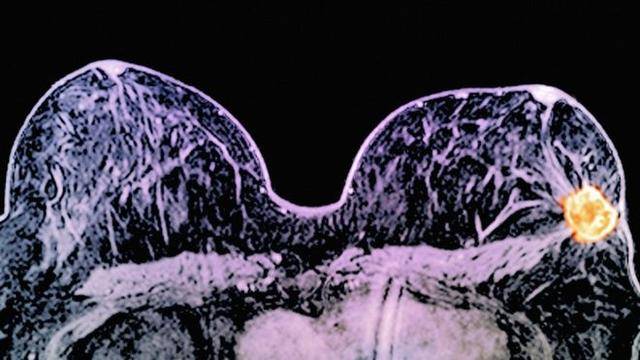

但是当作者们将人类癌症细胞转移到小鼠之中过后出乎意料地发现,那些表达E-cadherin的细胞在原发肿瘤中的存在更普遍。当肿瘤被移植到动物的乳腺或者是注射到血液之中后,这些表达E-cadherin的癌症细胞能够在转移后的次级位点逐渐建立起来,而不表达E-cadherin的细胞则几乎不能发生转移(图1a)。令人吃惊的是E-cadherin对转移性癌症细胞的存活可能具有非常重要的作用。

图1 E-cadherin调控浸润性导管乳腺癌转移的分子机制

Ewald研究组的工作揭示了E-cadherin通过帮助转移性癌症细胞克服由TGF-β以及ROS介导的细胞胁迫从而促进肿瘤发展以及转移的分子机制(图1b)。E-cadherin缺失通过影响细胞存活从而损害细胞的转移潜能,从而在次级位点损害肿瘤建立和细胞增殖。因此,关于浸润性导管乳腺癌的转移,E-cadherin促进癌症细胞存活的贡献超过了E-cadherin缺失促进侵袭性的优势。该工作鉴定出的E-cadherin促进癌症细胞存活的分子机制可能会为乳腺癌的治疗提供可能的参考思路。